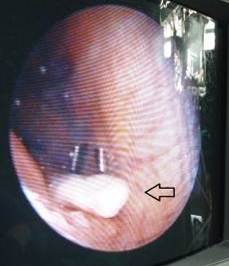

Una vez extraído el CLA (Figura 3), se realiza nuevamente la exploración artroscópica de la articulación para detectar la presencia de otros CLA y comprobar si está pediculado. La pieza extraída deberá ser enviada al departamento de Anatomía Patológica para determinar su composición histológica.25,30

En caso de no poder extraer el CLA por la vía artroscópica se procede a la artrotomía. Si se sospecha la presencia del CLA en la bolsa suprapatelar es conveniente colocar la rodilla en extensión y en caso de estar postero-medial o lateral es mejor colocar la articulación en flexión.12,13